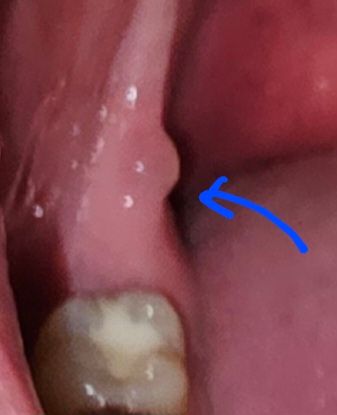

치킨을 먹고 어금니 뒷쪽에 물집이 생겼습니다

분명 치킨을 먹기 전에는 아무 것도 없었던 것 같은데 치킨을 먹고 난 직후이 어금니 뒷쪽에 이물감이 느껴져서 확인해보니 물집이 잡혀 있네요..

염증이나 농양 같지는 않고 바삭하고 자극적인 치킨을 먹다가 생긴 상처 등 단순 물집으로 추정되기는 하는데 혹시 치료가 필요할까요? 아니면 자연스럽게 터지도록 방치할까요?

점액종으로 보입니다. 점액종이란 점막내부에 조직액이 차게 됨으로써 생기게 되는데 물집과 비슷해요.

보통 마찰력이 많이 가해지거나 외부 자극이 되었을 경우에 생기는 경우가 많습니다.

시간이 지나면 자연스럽게 없어지지만 치과병원에서 간단하게 제거할수 있습니다. 자세한 확인을 위해서 치과병원에서 진료를 받아보세요.